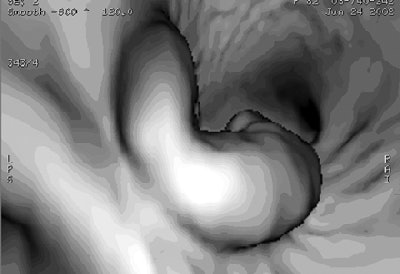

| Virtual Dissection (version 3.0, GE Healthcare) images of an 82-year-old man with ascending colon carcinoma seen at VC. Above, 360° virtual dissection image of right colon reveals lesion (arrow) that was considered to be a normal ileocecal valve. A 2.5-cm adenoma was found at colonoscopy. Normal valve can be identified in more proximal colon (arrowhead). Below, 3D endoluminal view shows colonoscopy-proven adenoma. Republished with permission of the American Journal of Roentgenology, from "CT colonography using 360-degree virtual dissection: A feasibility study," Johnson KT, Johnson CD, Fletcher JG, MacCarty RL, Summers RL, 2006 Jan;186(1):90-95. |